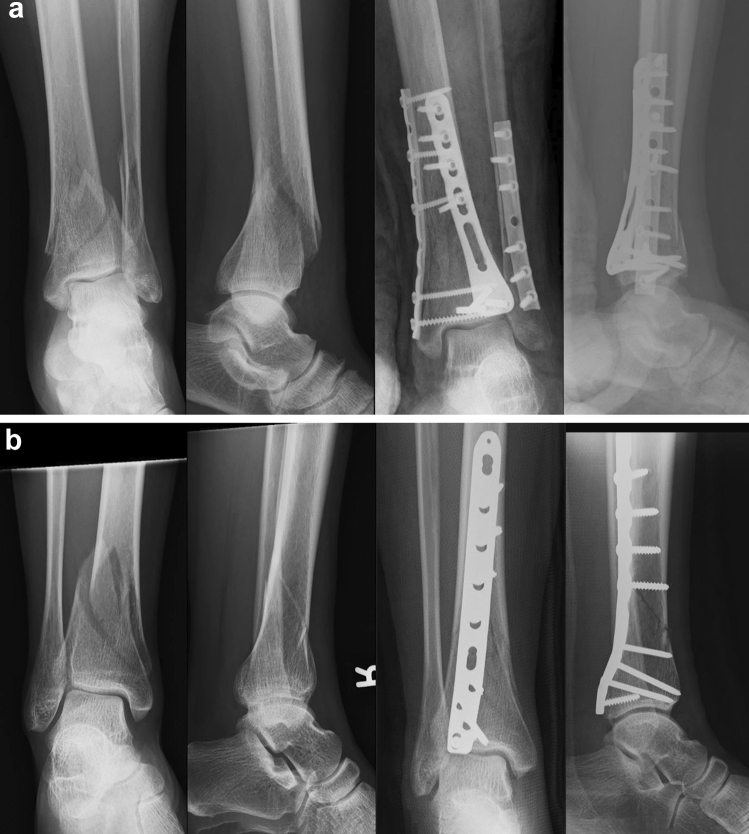

Posterolateral Plating of Distal Tibia Fractures Extending the Use of Walking Boot After Ankle Fracture The boot can be used for broken. Walking boots come in a variety of sizes, shapes, specialties, and constructions. A walking boot is a medical shoe that is designed to protect your lower leg, ankle, or foot after an injury. In a sporting environment, athletes are usually placed in a walker boot immediately after injury, regardless of the severity of. Walking Boot After Ankle Fracture.